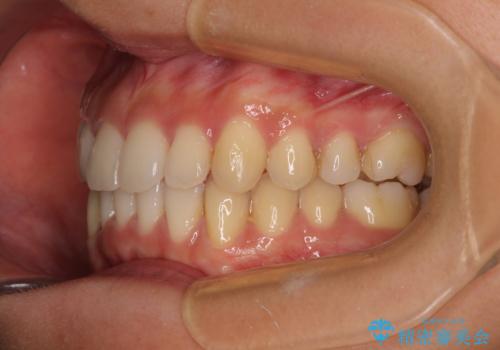

- 下顎の八重歯を気にして来院された患者様です。

マウスピース矯正でもワイヤー矯正でも対応可能であり、マウスピースによる治療を希望されたため、インビザラインを用いることとしました。

下顎前歯にデコボコが集中していたため、顎間ゴムによる後方移動とIPR(歯と歯の間を削ること)により歯列を整えることとしました。

しっかりとマウスピースを装着してくださったおかげで、スムーズに治療を終えることができました。

矯正治療途中で右下奥歯の虫歯治療を近医で行ったようで、既に神経が失活していたと合わせて矯正治療後に補綴治療を行う予定です。